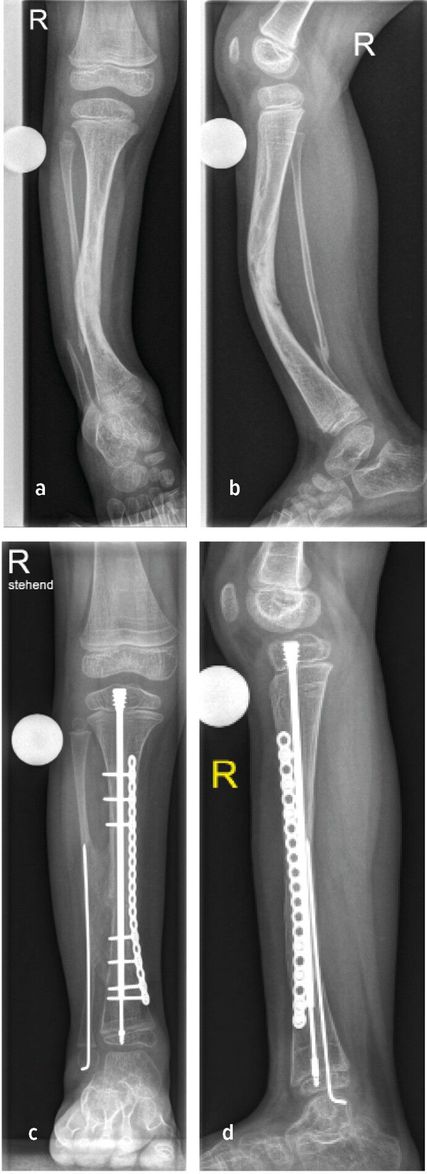

Die genaue Epidemiologie und Pathogenese des posteromedialen Bowings, auch bekannt als Crus valgum recurvatum, sind unbekannt. Einzelne dokumentierte Fälle in der Literatur lassen jedoch darauf schließen, dass es sich hierbei um eine sehr seltene Fehlstellung des Unterschenkels handelt, die vor allem die linke Extremität betrifft.15,16 Die Biegung der Tibia nach hinten und zur Körpermitte beträgt zwischen 25 und 70° und tritt typischerweise am Übergang vom mittleren zum distalen Drittel auf. In ausgeprägten Fällen kann die Fehlstellung bis zu 90° betragen. Der Fuß des Neugeborenen kann in schweren Fällen auf der Schienbeinkante zu liegen kommen. Bildlich repräsentiert dies der Fall eines 6 Wochen alten Mädchens mit posteromedialem Bowing der linken unteren Extremität mit typischer Biegung am Übergang vom mittleren zum distalen Drittel. Hier kommt der Fußrücken an der Unterschenkelkante zu liegen (Abb.3a,b). Differenzialdiagnostisch ist dabei an eine Calcaneo-valgus-Fehlstellung des Fußes zu denken.16 Eine spontane Rückbildung der Fehlstellung wird im Laufe des Wachstums bis zum 4.–5. Lebensjahr beobachtet.15 Konservative Maßnahmen beschränken sich initial auf sanfte Fußmassagen des Neugeborenen. In schweren Fällen kann eine graduelle Gipsredression eingesetzt werden.14

Abb. 3: 6 Wochen altes Mädchen mit posteromedialem Bowing der linken unteren Extremität (a+b) sowie postoperative Bildgebung

Verbleibende Fehlstellungen, insbesondere Rekurvation der Tibia, Beinlängendifferenz, Torsionsfehler oder Valgusfehlstellung der Tibia oder des Sprunggelenkes, bedürfen einer chirurgischen Intervention. Die dysplastische keilförmige Wachstumsfuge an der distalen Tibia begünstigt in einigen Fällen die Valgusfehlstellung im Sprunggelenk. Im Rahmen der Bildgebung präsentiert sich in dieser Abbildung ein 6 Jahre altes Mädchen mit einer selten auftretenden verbleibenden Valgusfehlstellung im Sprunggelenk bedingt durch eine dysplastische keilförmige Wachstumsfuge bei Z.n. Korrektur und Verlängerung mittels Fixateur externe und Stabilisierung mit intramedullärem Nagel (Abb.3c,d). Als chirurgische Therapien stehen hierfür die Wachstumslenkung an der distalen Tibia oder akute (supramalleoläre Korrekturosteotomien (Abb.3e,f) bzw. graduelle (externer Fixateur) Korrekturen zur Verfügung. Verbleibende Beinlängendifferenzen können durch eine Wachstumsbremsung der kontralateralen Seite bei geringer Beinlängendifferenz oder mittels gradueller Distraktionsosteogenese (externer Fixateur) therapiert werden.14,16,17